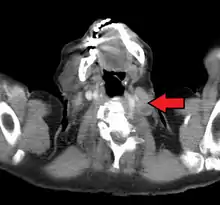

An enlarged Virchow's node as seen on CT

Malignancies of the internal organs can reach an advanced stage before giving symptoms. Stomach cancer, for example, can remain asymptomatic while metastasizing. One of the first visible spots where these tumors metastasize is one of the left supraclavicular lymph node.